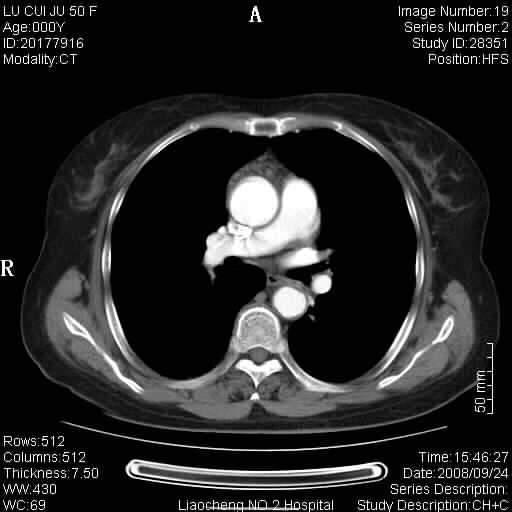

标题: CT15870:F50Y,纵膈占位,是不是胸腺瘤,请各位高手讨论。

临床表现为重症肌无力;ct增强扫描可见前纵膈胸腺部位弥漫性簇状软组织节结灶,不知道是不是胸腺瘤,请各位高手讨论。

胸腺外缘稍向外突,未见确切占位改变。结合临床考虑胸腺增生可能性大。